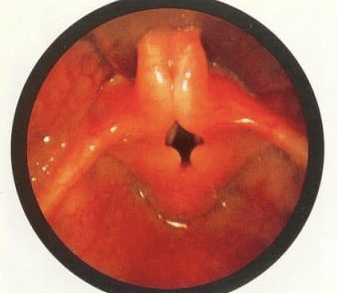

Diagnostic Flexible Nasopharyngolaryngoscopy (FNPLS) is a procedure used to visualize the larynx and assess the structural integrity of the tissues. During the procedure, a flexible scope is inserted through the nose or mouth and passed down into the throat to reach the larynx. This allows the healthcare provider to directly observe the larynx and identify any abnormalities.

In the case of laryngomalacia, laryngoscopy often reveals specific findings that confirm the diagnosis. The most common finding is the collapse of the supraglottic structures, which include the epiglottis, aryepiglottic folds, and false vocal cords. These structures may appear floppy, redundant, and prolapsed, leading to partial obstruction during breathing. The degree of collapse can vary, ranging from mild to severe.

In addition to assessing the structural aspects, laryngoscopy may also help identify any other associated conditions or anatomical abnormalities (secondary airway lesion/SAL) that could contribute to the symptoms. It allows the healthcare provider to evaluate the movement of the vocal cords, assess the presence of any anatomical obstructions, and determine the overall impact on breathing.